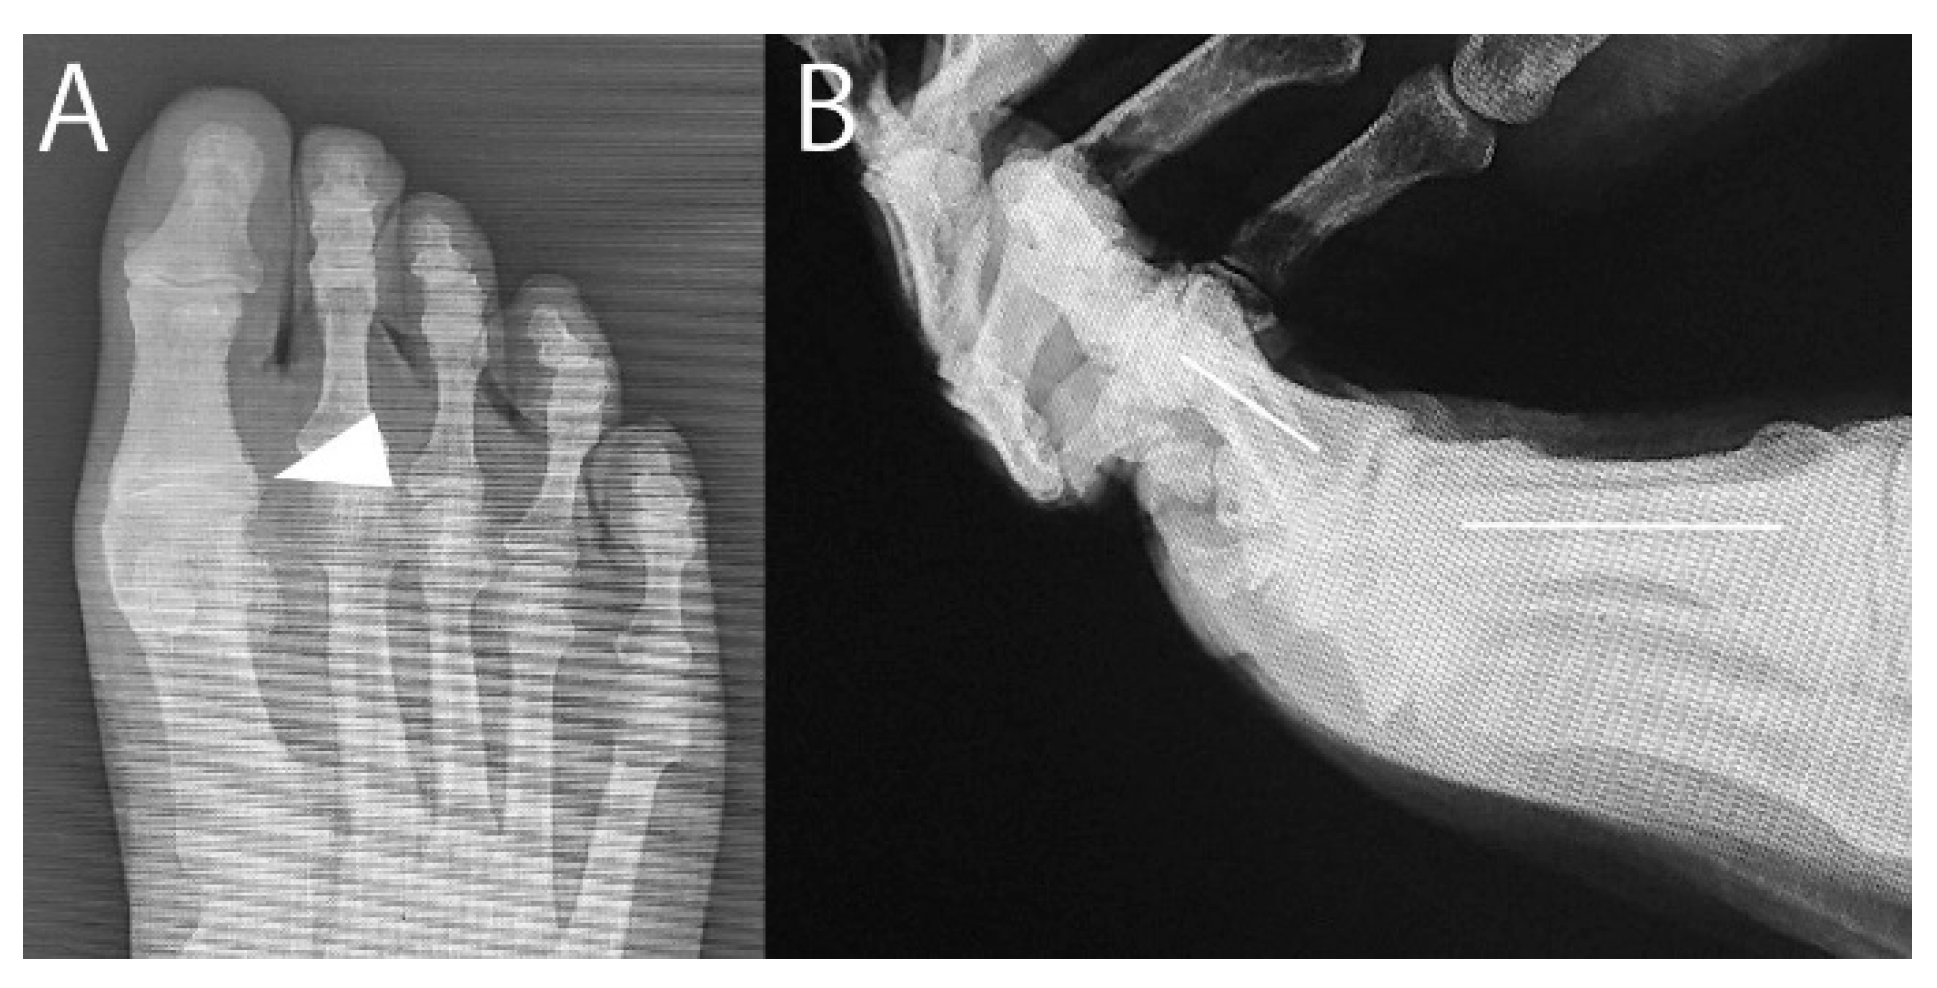

At 9 years postoperatively, contact was reestablished with the patient, who was still alive at 83 years old. He was able to follow-up at an orthopedist at nearby clinic, whose evaluation yielded VAS and JSSF scores were 0 and 88, respectively. The passive dorsiflexion angle on the lateral radiograph was 35° (Figure 5). Photographs of the right foot showed no postoperative cockup deformity of the hallux after cutting the FHB (Figure 6).

Figure 5. Radiographs at 9 years and 6 months postoperatively. (A) Anteroposterior image. Spurs at the lateral edge of the metatarsophalangeal joint were slightly enlarged compared with the preoperative radiograph (Figure 1A) (arrowhead). (B) Lateral image. The dorsiflexion angle was 35°. The joint space remained narrow, similar to the preoperative radiograph (Figure 1B).